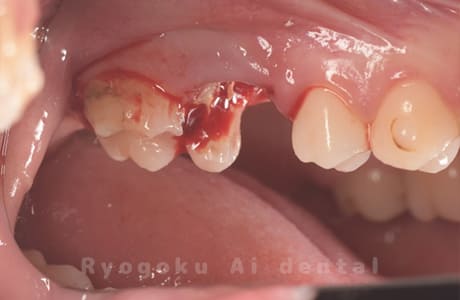

Case04

-

- 原因

- 重度カリエス、C3急化Pul

- 治療期間

- 約6ヶ月

- 治療内容

- 部分矯正、クラウンレングスニング、セラミッククラウン

- 治療費用

- 約350,000円

他院での説明で抜歯した後にインプラント治療を提案された患者さんです。虫歯が大きく、被せるための歯の長さが足りないため、埋まっている歯牙を引っ張り上げ、セラミックで被せたケースです。歯牙の状態も良好で、問題なく経過しています。